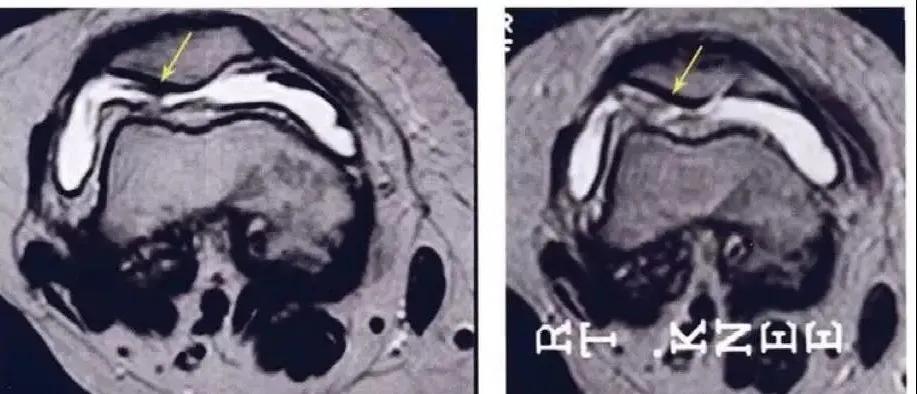

研究结果:关节内注射骨髓间充质干细胞6个月后 , 疼痛、功能状态和步行距离均提高 。 6名治疗组中3名患者在治疗前后的MRI比较可以看出 , 该治疗对于改善软骨厚度 , 修复组织延伸超过软骨下骨 , 以及减少软骨下骨的水肿是非常显著的 。

△ a示意治疗前软骨 , b为治疗后6个月软骨 , 箭头所示为软骨修复位置 。